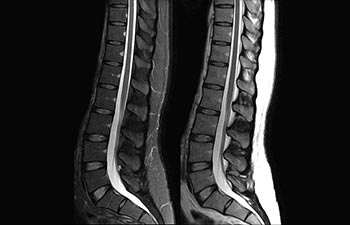

1De acuerdo con un estudio interno en el que se compara el flujo de trabajo con el equipo de RM Achieva. 2 ComforTone estará disponible con Prodiva 1.5T en el cuarto trimestre de 2017 3 De acuerdo con un estudio interno donde se compara el flujo de trabajo en una combinación de aplicaciones cerebrales, musculoesqueléticas, de columna y de cuerpo con el equipo de RM Achieva 4 La operación normal se define como una adquisición típica realizada con suministro continuo de electricidad, así como de refrigeración del imán, sin incluir las actividades de servicio 5 En función del contrato y de la disponibilidad local 6 Con "otros equipos de RM" nos referimos a equipos de RM de 1,5 T de 60 cm para exámenes de cuerpo entero